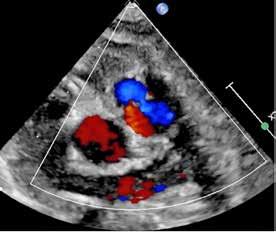

Issuu converts static files into: digital portfolios, online yearbooks, online catalogs, digital photo albums and more. Sign up and create your flipbook.